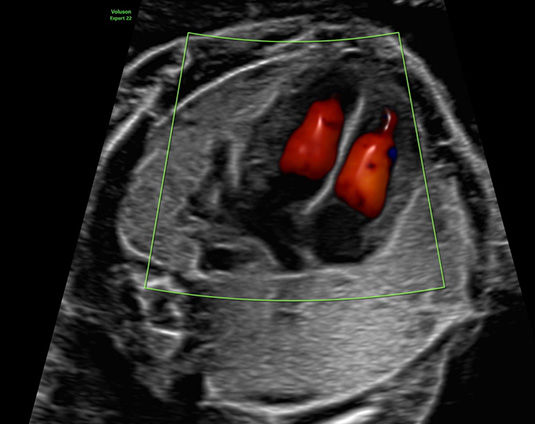

Die Herzechokardiografie ist eine ausführliche Untersuchung des kindlichen Herzens, in der die Entwicklung und die Funktion beurteilt werden. Der optimale Zeitpunkt für die Untersuchung ist die 20.-22. Schwangerschaftswoche. Es ist aber auch möglich im Rahmen der frühen Fehlbildungsdiagnostik (Ersttrimesterscreening) eine detaillierte Herzbeurteilung durchzuführen. Beurteilt werden die Lage und Größe des Herzens, das Aussehen und die Funktion der Herzkammern und Herzklappen sowie der zuführenden Venen und abgehenden Gefäße. Durch die gezielte Echokardiographie mit Farbdoppler, gepulstem Doppler und M-Mode lässt sich der Großteil aller angeborenen Herzfehler erkennen. Die Voraussetzungen hierzu sind eine spezielle Ausbildung und Erfahrung des Untersuchers und eine hohe Qualität des Ultraschallgerätes.